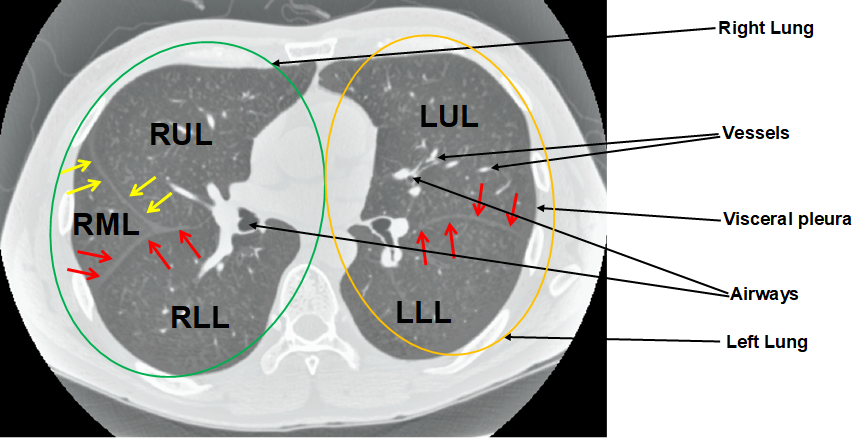

We argue that the sub-optimal paradigm of processing different abstractions within a single CNN pipeline can be remedied through the effective processing of information in a structured manner. Consequently, we devise strategies for disentangling the edge and texture information within a single training pipeline. Figure 2 illustrates how our proposed module, dubbed EG-CNN, can be paired with any existing CNN encoder-decoder to improve segmentation quality near intensity edges. We have applied our EG-CNN to the tasks of brain and liver tumor segmentation in medical images (Figure 3).

(1) Brain MR (2) Liver MR (3) Liver CT (4) Lung CT